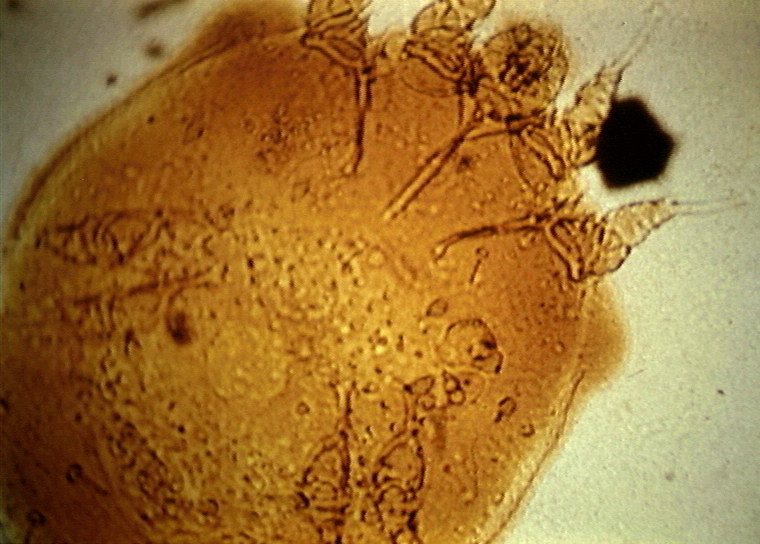

| o_Sarcoptes[1].jpg | 2010-01-15 17:58 | 34K | ||